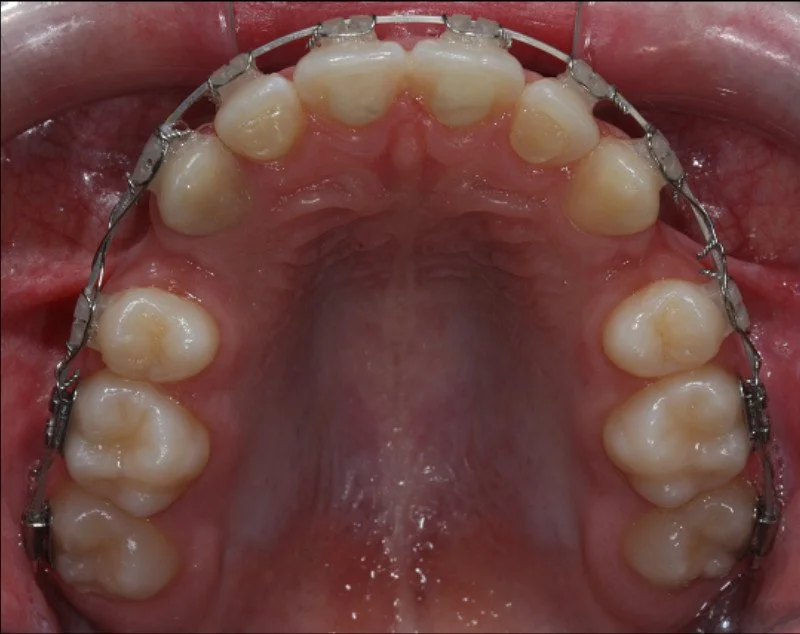

CASO ESTRATTIVO

In alcuni casi, per allineare correttamente i denti senza creare problemi come recessioni gengivali o danni all’osso di supporto, è necessario ricorrere a estrazioni strategiche. Questo accade quando lo spazio in arcata è insufficiente per accogliere tutti i denti in una posizione stabile e armoniosa. Estrarre alcuni elementi dentari permette di ottenere un risultato estetico e funzionale migliore, garantendo una masticazione corretta e preservando la salute dei tessuti gengivali e ossei.

BEFORE

Trattamento con 4 estrazioni di una malocclusione di classe II con proclinazione degli incisivi superiori e inferiori.